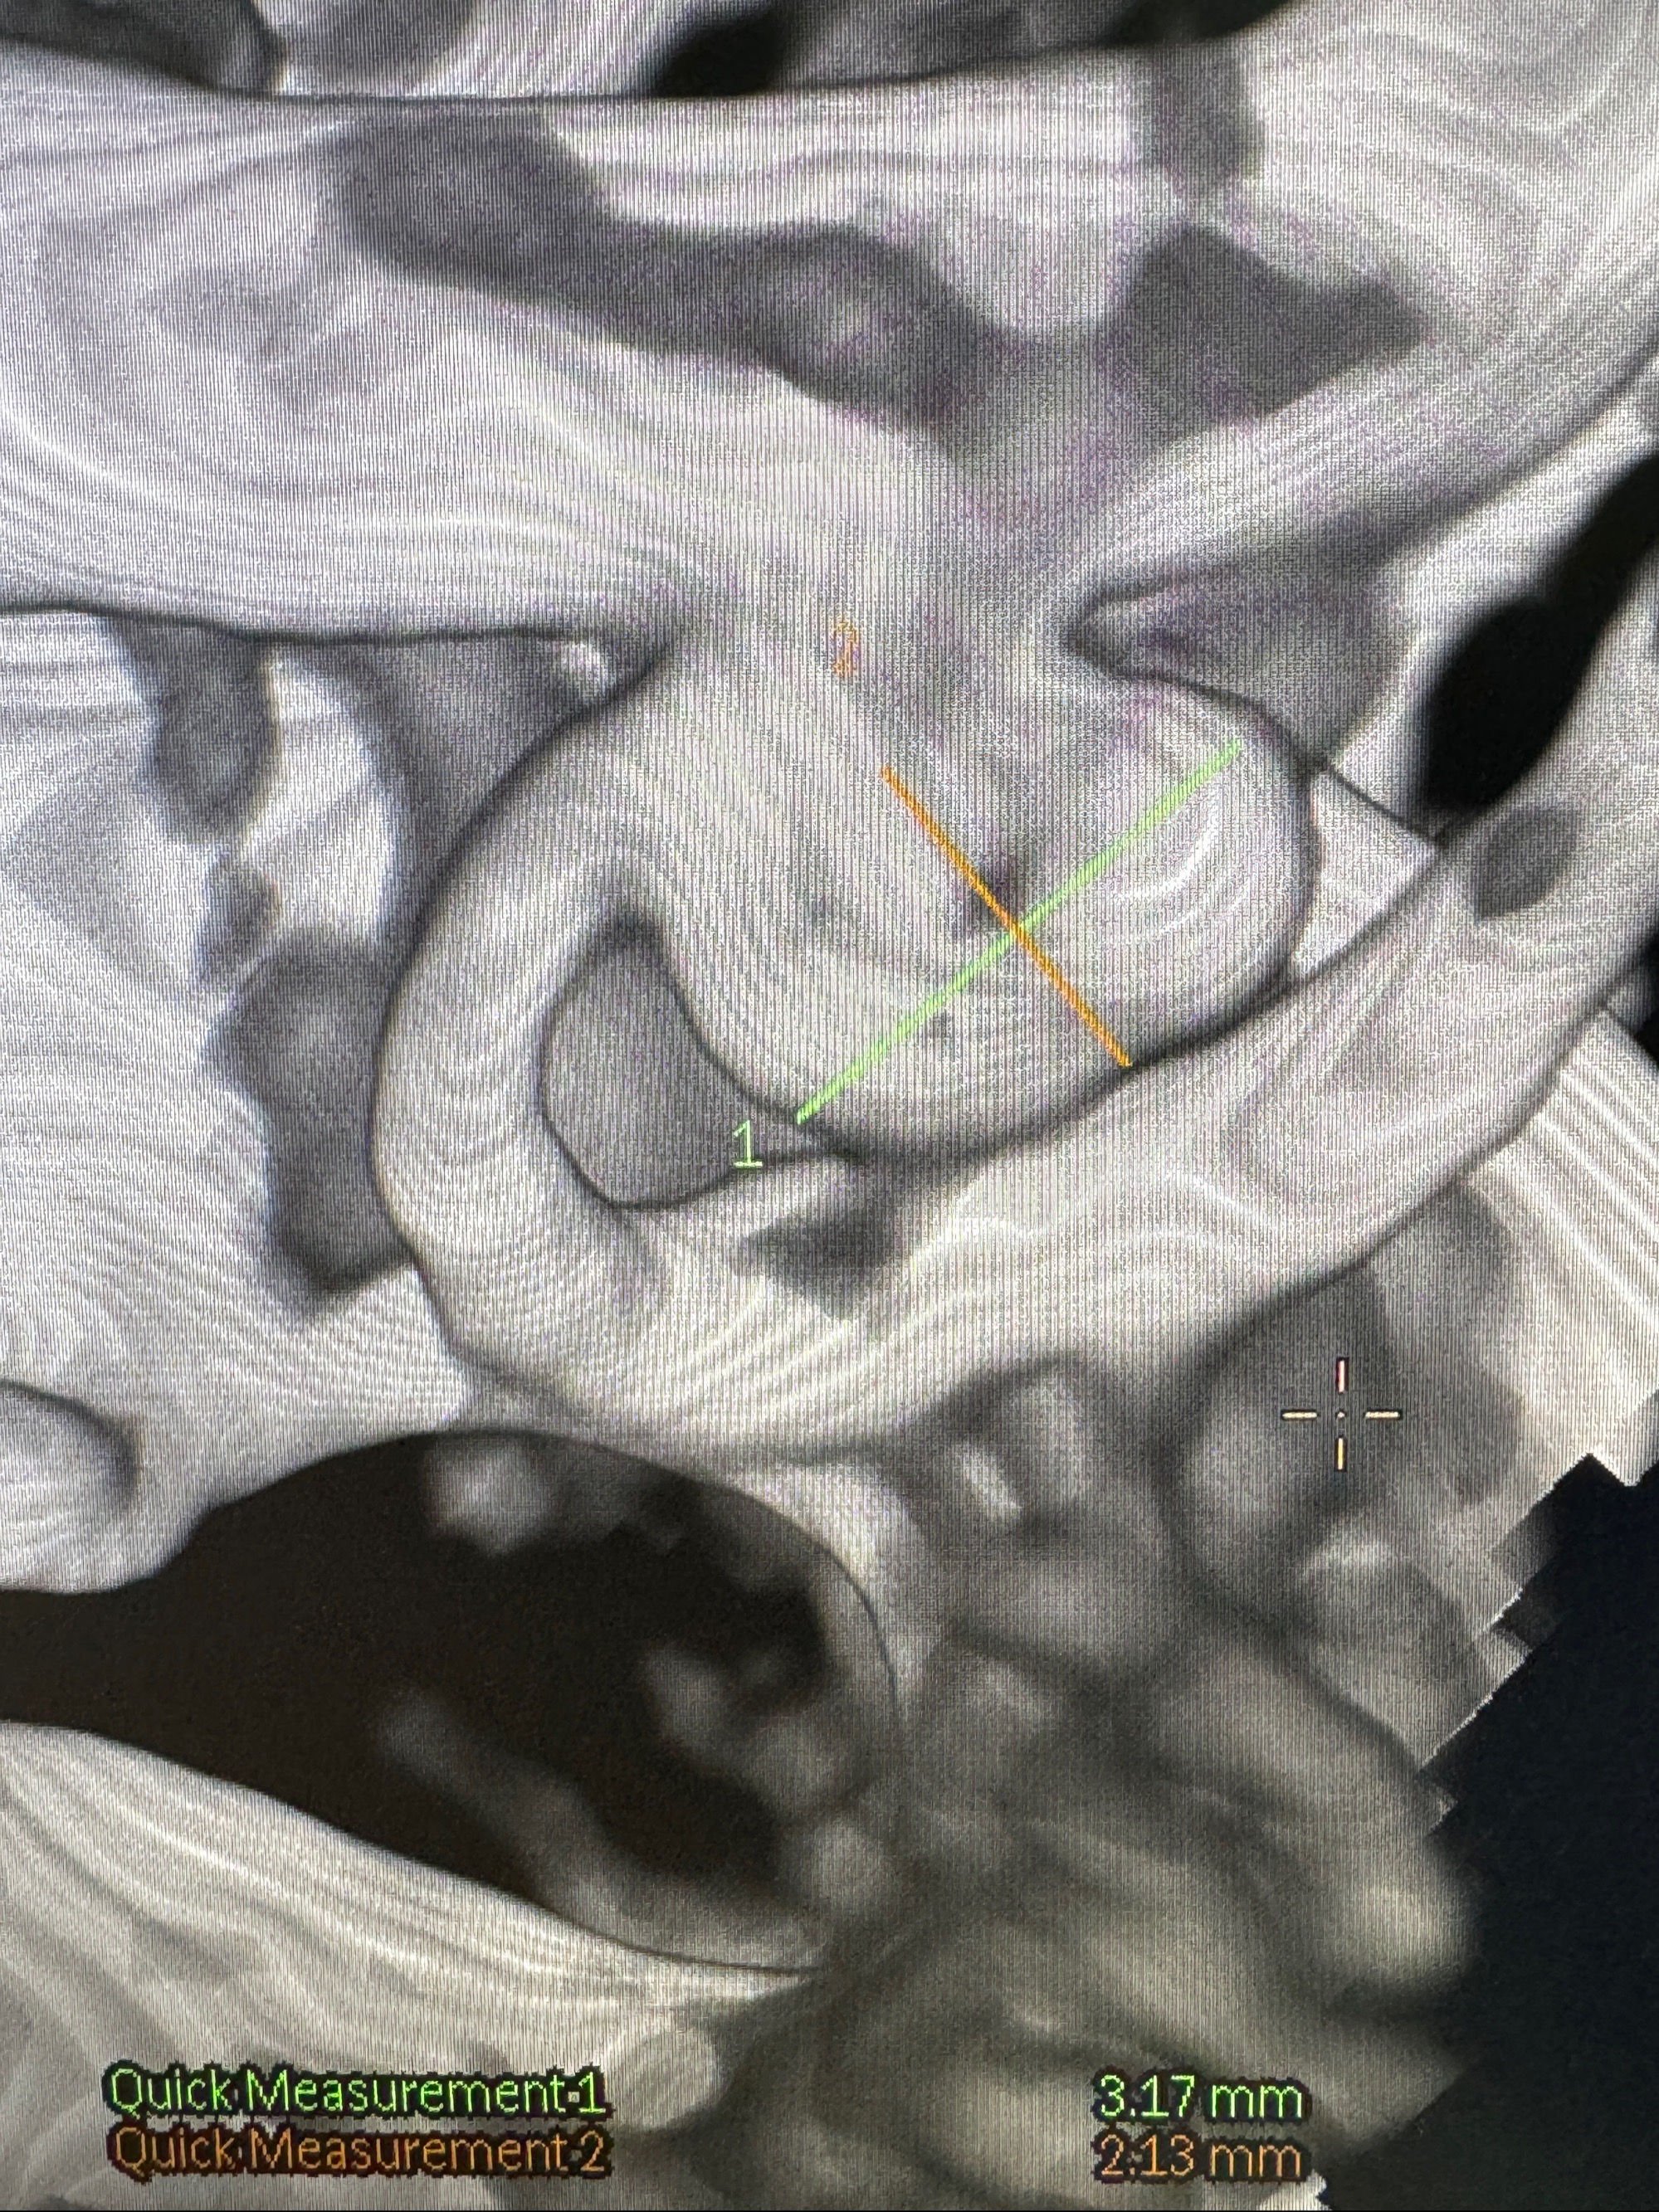

2023-11-24DSA:右侧大脑中动脉下干起始部动脉瘤,约2.3*2.5mm,形态规则

2023-12-04全麻下行支架辅助治疗

S-AB4-20mm